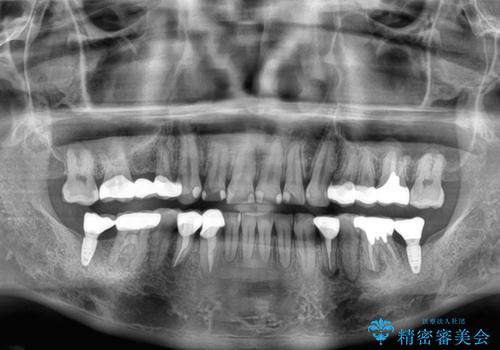

矯正治療にやや時間がかかりましたが、歯列はきれいに整い、気になっていたむし歯や銀歯は自然な色合いに仕上がりました。